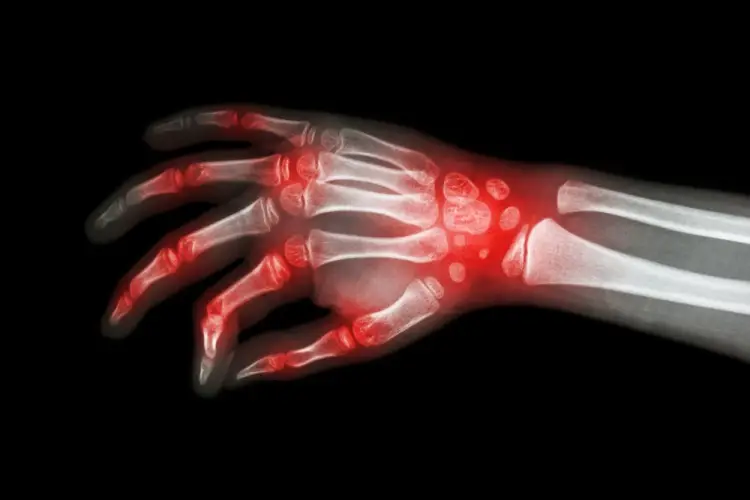

تطلق كلمة الأمراض الروماتيزمية عند الأطفال أو التهاب المفاصل على مجموعة من أمراض المناعة الذاتية والالتهابات التي قد تصيب الصغار وعلى الرغم من تشابه الأعراض الأساسية مثل آلام المفاصل وتورمها واحمرارها، إلا أن لكل نوع من هذه الأمراض سمات خاصة قد تمتد لتؤثر على العين أو الجلد أو الجهاز الهضمي. ومن أبرز أنواع الروماتويد عند الأطفال ما يلي:

يسبب هذا المرض التهاب مستمر في مفصل واحد أو أكثر، ويصاحبه أعراض مثل التورم والألم والتيبس، خاصة في فترات الصباح أو بعد الراحة، وقد يمتد تأثيره ليشمل النمو والحركة إذا لم يتم تشخيصه وعلاج الروماتويد عند الاطفال مبكرًا ومع ذلك، فإن الاكتشاف المبكر واتباع الخطة العلاجية المناسبة يساعدان على السيطرة على المرض وتحسين جودة حياة الطفل بشكل كبير.

تختلف أعراض الروماتويد الخفيف عند الأطفال من حالة لأخرى، إلا أنها غالبًا ما تشمل ألمًا وتورمًا وتيبسًا في المفاصل، وقد تظهر هذه الأعراض في مفصل واحد أو أكثر وتستمر لمدة لا تقل عن 6 أشهر ومن المهم إدراك أن تأثير الروماتويد لا يقتصر على المفاصل فقط، إذ يمكن أن يمتد ليصيب أجهزة أخرى في الجسم، حيث قد يعاني بعض الأطفال من أعراض مناعية جهازية مثل الحمى، الطفح الجلدي، والشعور المستمر بالتعب.

ومن أبرز العلامات المبكرة للروماتويد عند الأطفال:

- ألم وتورم في المفاصل.

- تيبس صباحي أو بعد فترات طويلة من الراحة.

- سخونة واحمرار حول المفصل المصاب.